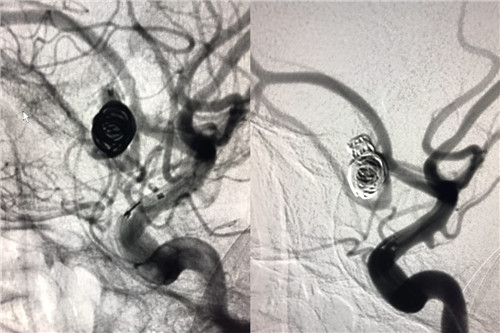

术前造影

术中造影